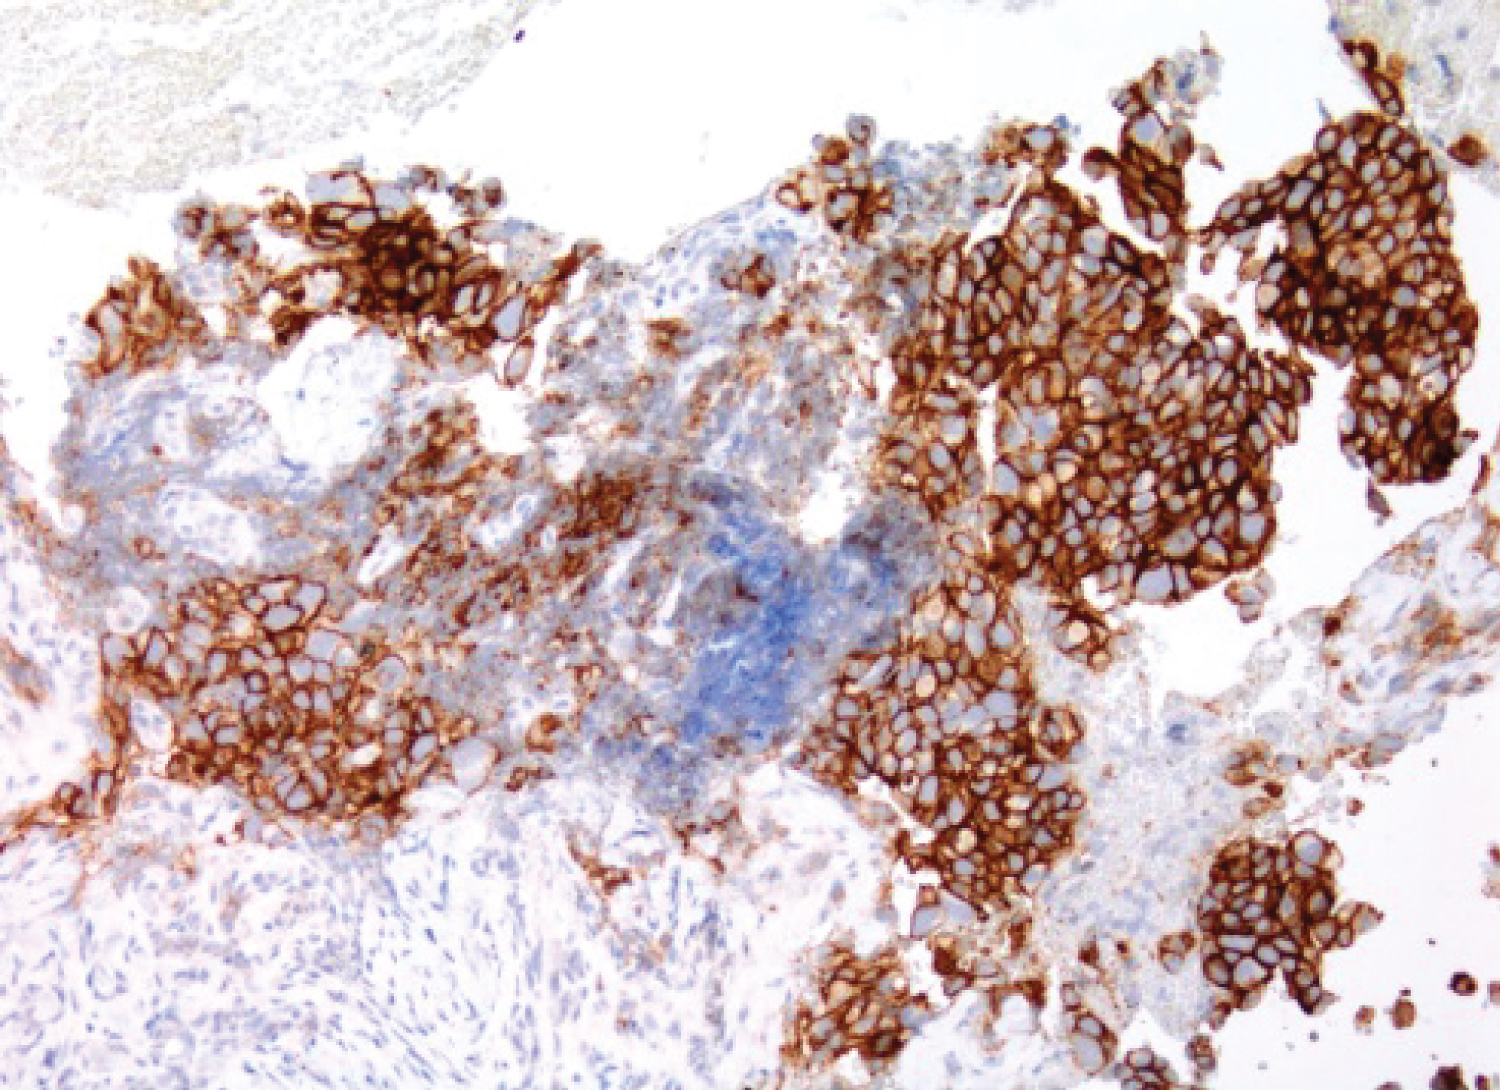

Lung adenocarcinoma subtypes have been defined by the 2011 International Association for the Study of Lung Cancer (IASLC) classification, and these criteria were adopted in the 2015 WHO classification [1]. In this study, we found that majority of squamous cell carcinoma display either negative or low expression of PD-L1 protein detected by IHC, regardless of its degree of differentiation (see Figure 1). In adenocarcinomas, however, tumors with PD pattern show high PD-L1 expression, with pure solid adenocarcinoma has the highest expression level (see Figure 2 and Figure 3). The degree of expression becomes lower when combined with other growth patterns of better differentiation. On multiple cases (n = 13), the clinicians requested the test to be performed on small cell carcinoma, and they all showed negative expression of PD-L1 [2,3]. As intratumoral inflammatory cells also express PD-L1, one should be cautious when interpreting PD-L1 expression to avoid false positive calls (see Figure 4). A known limitation to this study is we evaluated the PD-L1 expression only on the available material tested, which in most instances was either a cell block from cytology specimen, or a core needle biopsy. The available material might not accurately reflect the full picture of the entire tumor, especially if it is a tumor with mixed growth patterns, but also keeping in consideration that in such advanced disease with metastases the initial tested material will not be followed by a generous resection, and even with a wedge resection or lobectomy specimens, the test was never repeated. However, some studies have shown a strong correlation between PD-L1 expression in cytologic and surgical specimens [4]. The value of this study is to provide some opinion about the behavior of the tumor cells in regards to the degree of PD-L1 expression as early as the H&E slides examination level, which could be of some relevance to the clinical team. The other value is to evaluate the response of the patient to the immunotherapy provided when the tumor has mixed growth patterns, predicting that some resistance or ineffectiveness might be related to other components of the tumor. Neuroendocrine neoplasms of the lung, as a component of non-small cell lung cancer, were not investigated in this study. A recent study [1] studied the expression of PD-L1 compared to clinicopathologic features of tumor cells, as well as tumor infiltrating immune cells, using SP142 clone. To our knowledge, this is the first study to be performed on a well-rounded variety of specimens, including cytologic and tissue biopsy specimens, with sources varying between primary lung and metastatic sites. It is also the first study run in a big cancer institution using the FDA approved 22C3 clone antibody and the FDA approved Dako 48 autostainer. The correlation of PD-L1 expression with histologic grade and solid subtype may be clinically useful. Currently, frontline use of Pembrolizumab (Keytruda) in advanced lung cancer is limited to patients with high expression of PD-L1 [1]. In patients with NSCLC showing solid growth pattern or with other patterns of poor differentiation, initiating treatment early will be of benefit. In patients with a small biopsy that is negative for PD-L1 expression but with clinicopathologic features that would suggest a high probability of PD-L1 expression, re-biopsy might be considered to assure that patients who are candidates for frontline immune checkpoint inhibitors are not missed [1]. As for the correlation with available immune checkpoint inhibitors, although we have few patients with reported complete and partial responses who had tumors with "high-expression" PD-L1, it is still early to evaluate the full advantage of treatment in these patients. However, noticing good responses in patients with high-expression tumors gives hope to more patients, and indicates that more research is still needed in this direction.

Figure 4: 54 F, SCC, keratinizing, metastatic to LN. All strongly positive staining cells are peritumoral macrophages, rather than tumor cells. View Figure 4